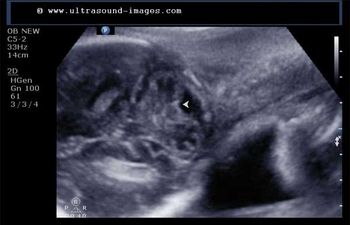

This 53 year-old woman has a uterine lesion and irregular bleeding. Which of the following is the correct diagnosis?